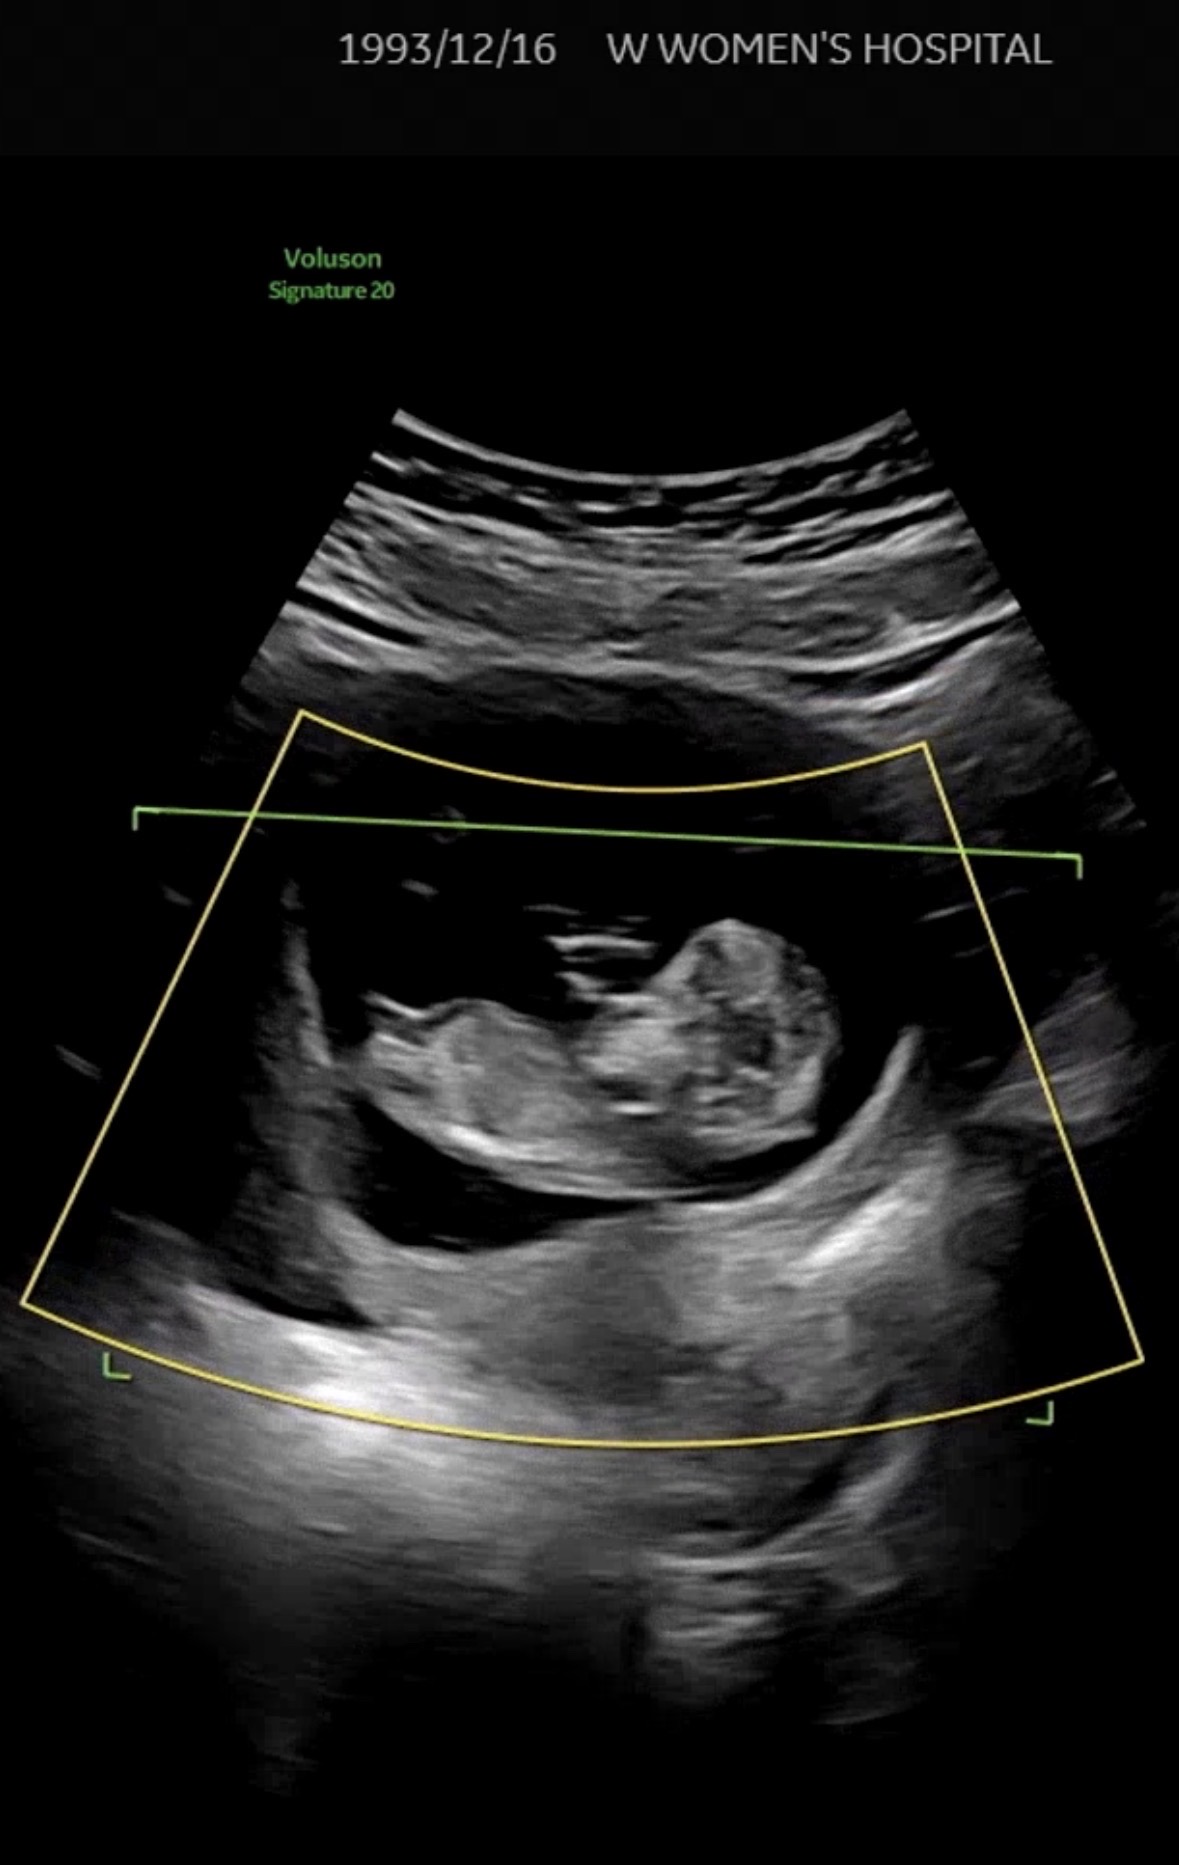

최대한 선명하게 나온사진인것같은데 맞나용?̊̈ 각도법 고수님들 투표 부탁드려요 ㅎㅎ 챗지피티랑 빌리는 딸이라고 하는데 남편은 아들같대요 ㅎㅎ